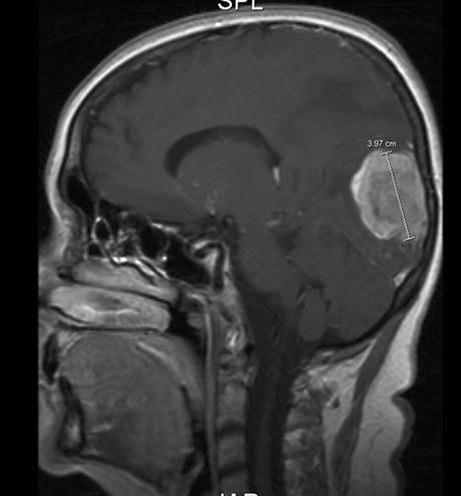

MR er den mest sensitive undersøkelsen såvel til påvisning av små metastaser som til å påvise andre sykdommer i hjernen. Ved CT av hjernen med kontrast finnes multiple hjernemetastaser hos ca. 50 prosent, ved MR-scanning hos ca. 75 prosent.

En operasjon gir ofte rask lindring av symptomer som skyldes økt trykk inne i hjernen. Fjerning av store svulster forbedrer ofte kognitiv funksjon og lindrer nevrologiske utfall, samt benyttes til diagnostisk bekreftelse og eventuelt gentesting for å finne frem til mer målrettet medikamentell behandling. Kirurgi kan bedre overlevelsen særlig hos pasienter med enkeltstående, store (> 3 cm) og symptomgivende metastaser.